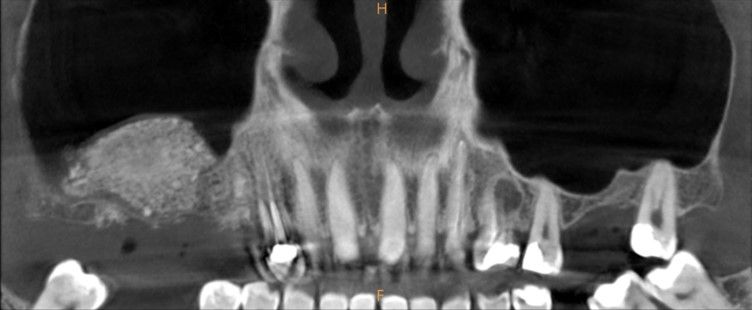

En la exploración radiográfica mediante escáner se apreció una lesión apical de pequeño tamaño en el 1.4 y una escasa disponibilidad ósea. Además, se observó imagen radioopaca cupuliforme de 3 x 2,8 cm en el seno maxilar derecho, compatible con un pseudoquiste sinusal (Figura 2). La extensión craneal alcanzaba la mitad superior del seno maxilar y el volumen de la lesión (5 cm³) era aproximadamente ⅓ del volumen sinusal (Figuras 3 y 4).